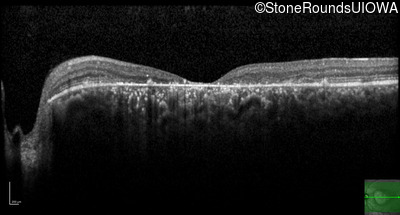

Optical Coherence Tomography - Left -

20/125

Exemplar / OCT Stack